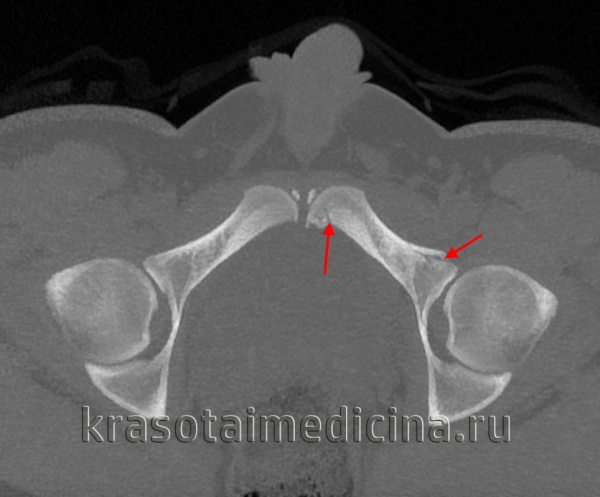

По направлению повреждающей силы выделяют переломы костей таза вследствие переднезаднего сдавления (АРС), бокового сдавления (LC), вертикального (VS) и комбинированного воздействия (СМ). Согласно классификации Тайля (Tile), все переломы подразделяются на три группы — А, В и С (включающие пронумерованные подгруппы) — на основании тяжести повреждения связочного аппарата и костей.

- Компьютерная томография.